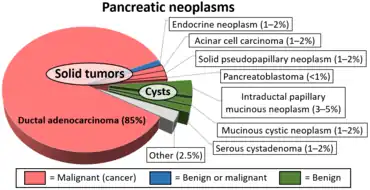

Diagram by Mikael Häggström, M.D.